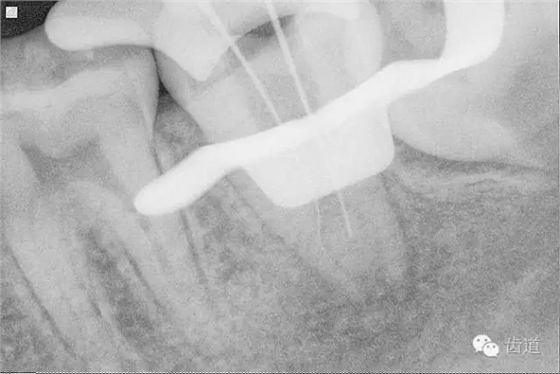

9. 預(yù)彎初尖銼探入根管

10. X線根尖片示尖 (近中及峽部)

17. X線主尖片